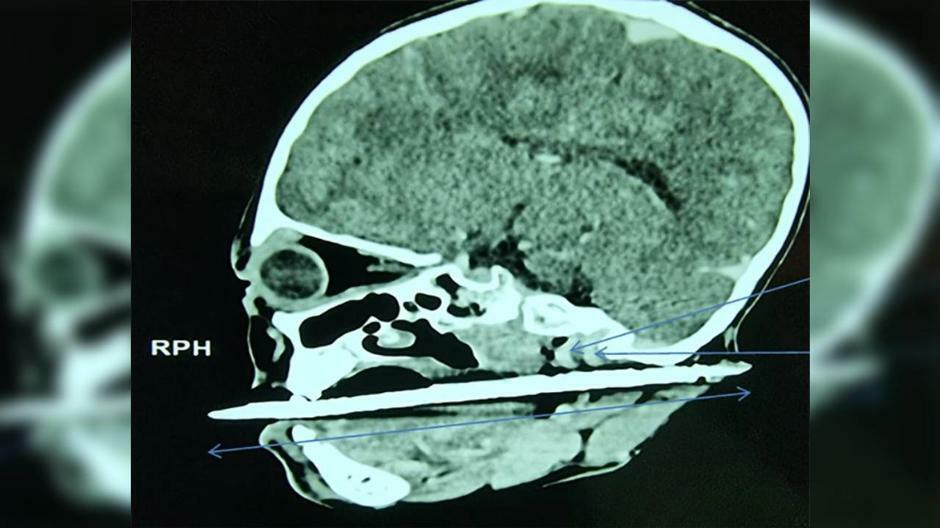

根據《RTL NEWS》報導,女童跌倒後,髮簪直接刺穿口腔,刺到頭部再從耳後出來,頭無法轉動、嘴巴也閉不起來,當場血流如注,被送往附近的醫院搶救。事後,醫師透過X光發現,女童的傷口雖靠近頸內動脈和頸靜脈,但重要器官和血管沒有大礙,趕緊開刀取出髮簪,成功將命救回來。

圖片來源/RTL NEWS